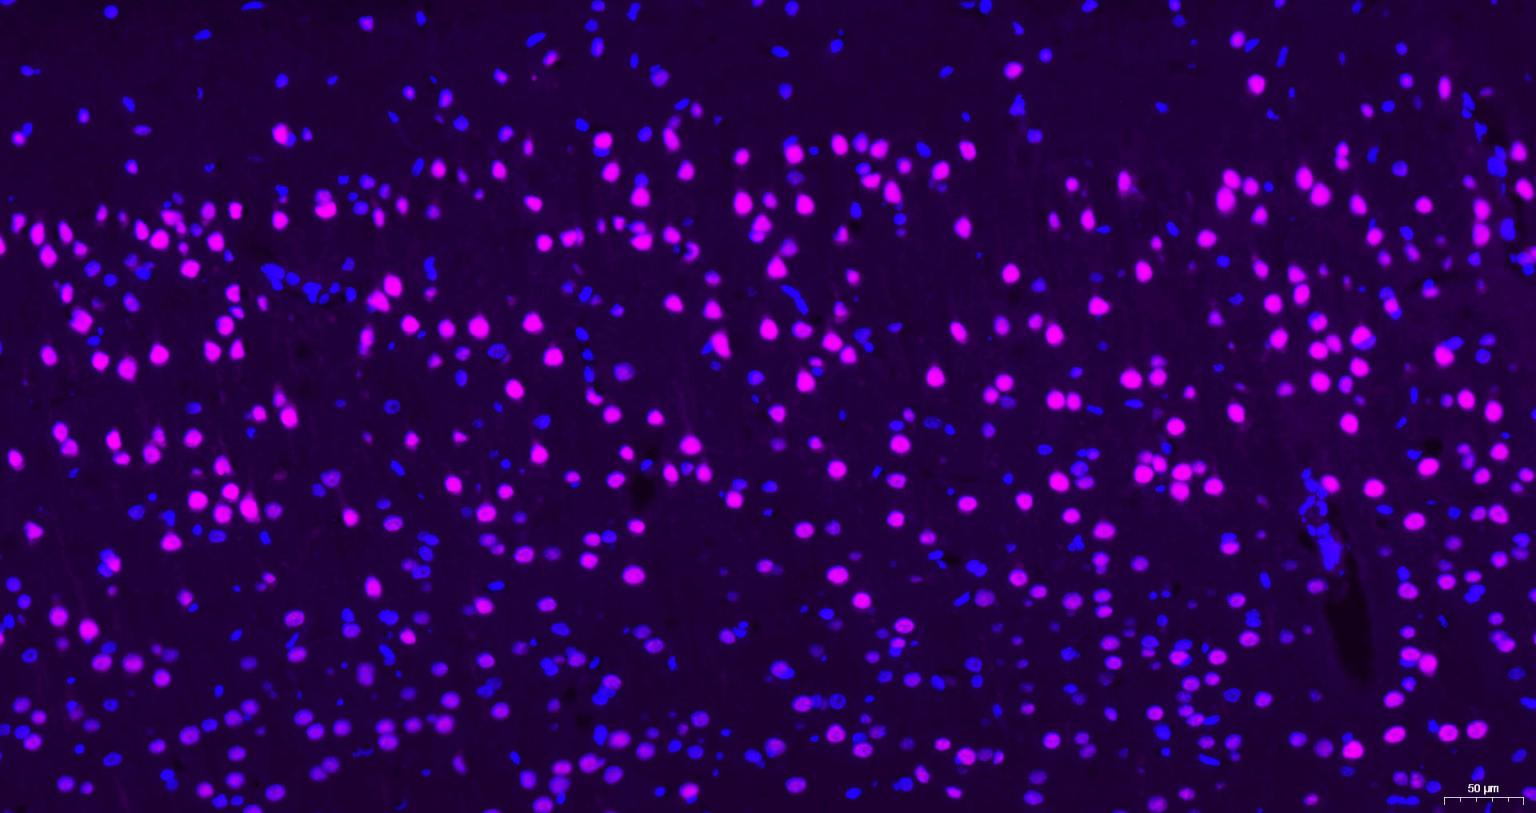

Paraformaldehyde-fixed, paraffin embedded Human brain; Antigen retrieval by boiling in sodium citrate buffer (pH6.0) for 15 min; Antibody incubation with AKT1 Monoclonal Antibody, Unconjugated(bsm-52010R) at 1:200 overnight at 4°C, followed by a Cy5 conjugated Goat Anti-Rabbit IgG (bs-0295G-Cy5)antibody at 37°C for 90 minutes, DAPI (blue, C02-04002) was used to stain the cell nuclei.